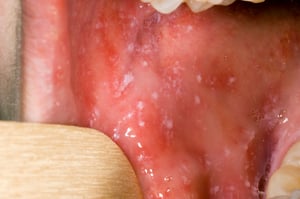

Antes de que comience la erupción, pueden aparecer manchas de Koplik dentro de la boca. Las manchas de Koplik son pequeñas manchas de color rojo brillante con centros blancos o blanco azulados. Los centros pueden parecerse a granos de arena.

Las manchas de Koplik son manchas rojas brillantes con centros blancos o azulados que se asemejan a los granos de arena. Pueden aparecer en cualquier parte de la boca en personas con sarampión.

Las manchas de Koplik son manchas rojas brillantes con centros blancos o azulados que se asemejan a los granos de arena

Imagenes cortesía del Public Health Image Library of the Centers for Disease Control and Prevention.